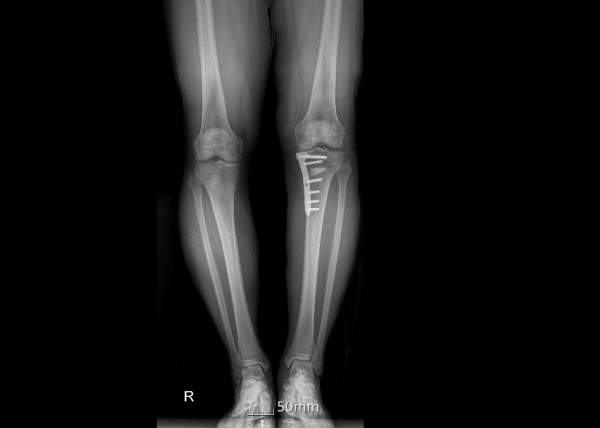

#절골수술(Osteotomy)의 이해

절골수술은 무릎 관절의 비정상적인 정렬을 교정하기 위한 수술적 방법입니다. 이 수술은 주로 관절염으로 인한 통증과 기능 장애를 겪고 있는 환자들에게 시행됩니다. 수술 과정에서는 뼈를 절단하고 재정렬하여 무릎에 가해지는 압력을 분산시킴으로써, 관절에 대한 스트레스를 줄이고 통증을 완화시킵니다. 이러한 접근법은 관절의 수명을 연장시키고, 궁극적으로는 관절 교체 수술을 피할 수 있게 해줍니다.